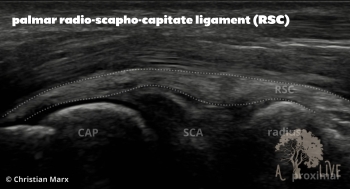

carpal ligaments